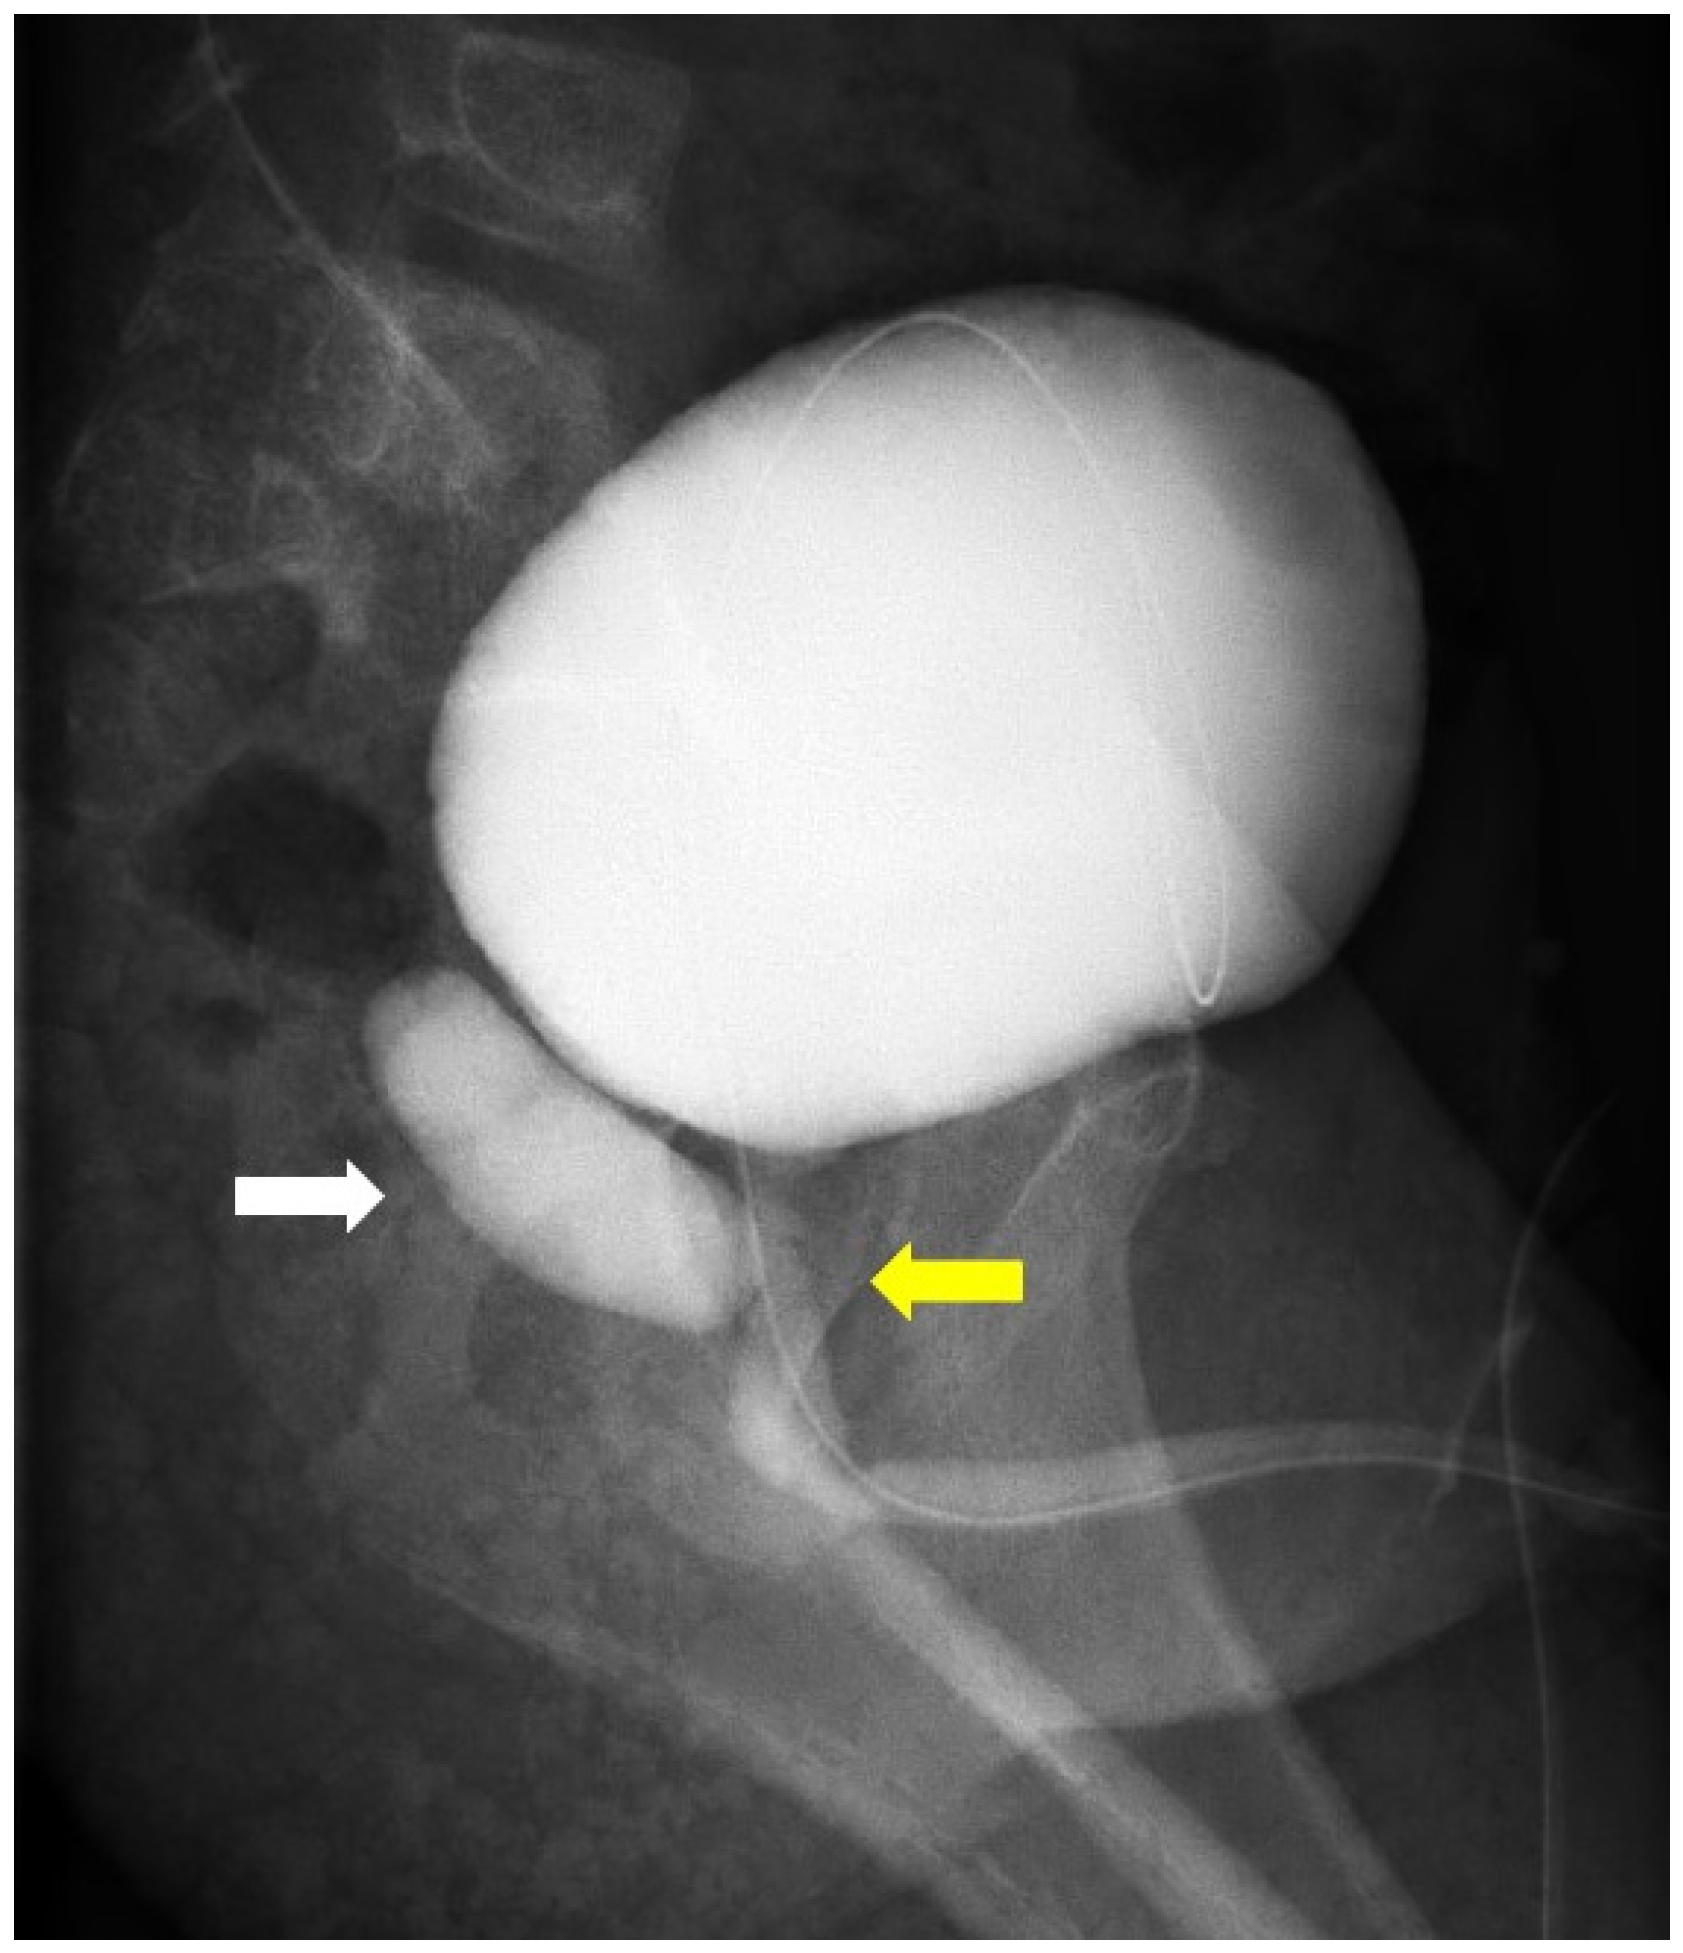

2. Case Presentation